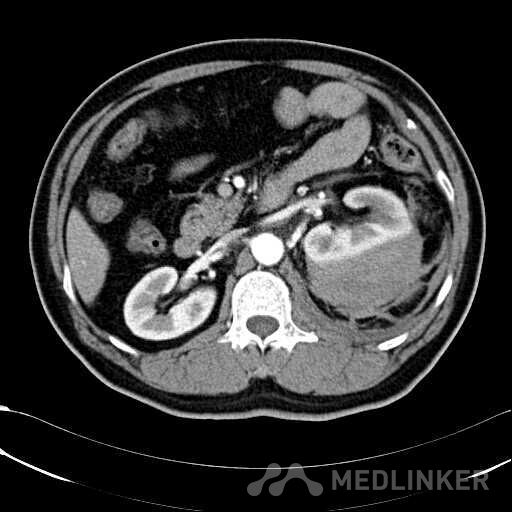

患者是54岁男性 主 诉: 突发左腰部疼痛3小时。 现病史: 缘于入院前3小时患者无明显诱因出现左腰部剧烈疼痛,无向他处放射,与活动及体位无明显关系,伴有腹胀、恶心、呕吐,无头痛、头晕,无人事不省、口吐白沫,无胸闷、胸痛、咯血,无发热、畏冷、寒战,大小便未解,肛门无停止排气,遂就诊我院,查“泌尿系彩超:左肾实质及不均质回声区,范围约9.4*4.1cm,界不清,内未见明显血流信号”,为进一步治疗,门诊拟“左肾占位”收住入院,发病以来,患者精神欠佳,未进食,大小便如前述,体重无明显改变。 患有“高血压病”7年,规则服药治疗(具体不详),监测血压情况不详。 T: 36.5 ℃ P: 65 次/分 R: 20 次/分 BP: 154/94 mmHg 双肾区皮肤无红肿、破溃及隆起,双肾肋下均不能被触及,左侧肾区叩击痛明显,右侧肾区无叩击痛,双侧肾区未闻及血管杂音。膀胱区无隆起,无压痛,耻骨上膀胱区叩诊空虚。外生殖器发育正常。 2016-04-12 泌尿系彩超:左肾实质及不均质回声区,范围约9.4*4.1cm,界不清,内未见明显血流信号。 04-12血常规:血红蛋白 151 g/L,白细胞 16.80 10^9/L,中性粒细胞百分比 84.90 %。急诊生化:白蛋白 39.8 g/L,葡萄糖 9.46 mmol/L。